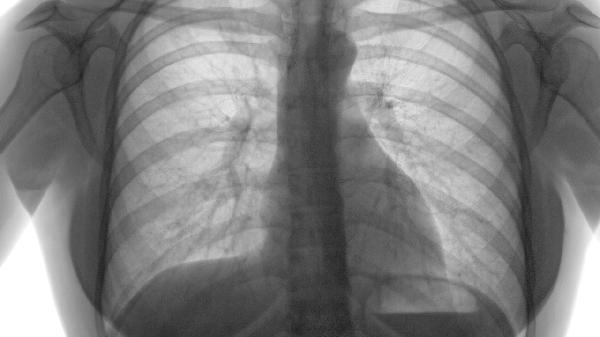

石仙桃对肺有一定益处,可作为辅助调理的药材使用。石仙桃具有润肺止咳、清热化痰的功效,适用于肺热燥咳、痰黏难咯等症状。

石仙桃含有黄酮类、多糖等活性成分,能帮助缓解呼吸道炎症,改善干咳症状。其润肺作用对秋季燥邪伤肺引起的咽喉干痒、声音嘶哑有调理效果。民间常将新鲜石仙桃与冰糖炖煮,用于缓解儿童百日咳或慢性支气管炎患者的夜间呛咳。对于长期吸烟或接触粉尘的人群,用石仙桃泡水代茶饮可起到一定的肺部养护作用。

需要注意的是,石仙桃性微寒,脾胃虚寒者慎用。其止咳作用主要针对燥咳,风寒咳嗽或痰多清稀者不宜使用。肺结核、肺纤维化等器质性疾病患者须配合正规治疗,不能单靠石仙桃调理。部分人群可能对石仙桃过敏,初次食用应观察是否有皮疹、腹泻等不良反应。